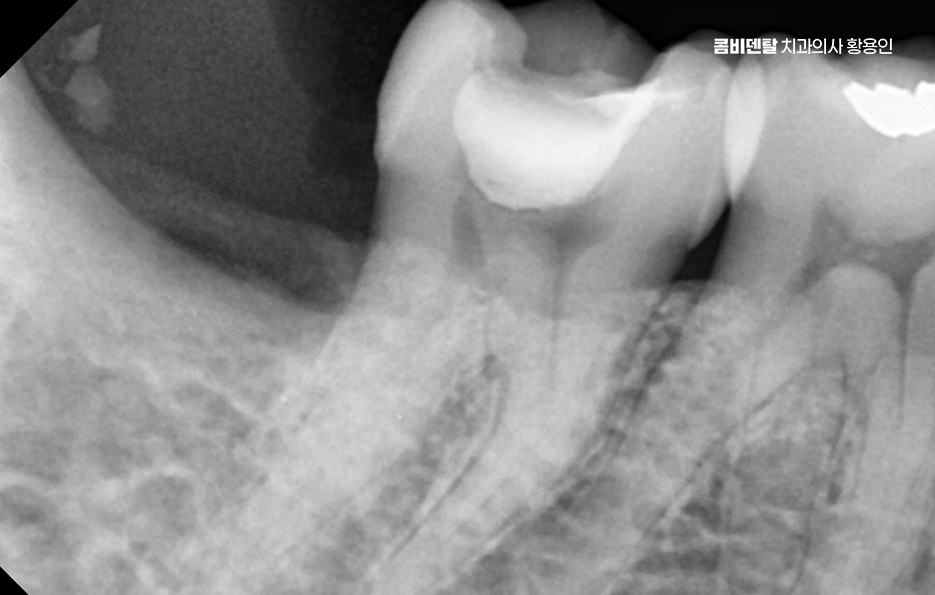

지금도 입 안에 아말감이 남아 있는 분들이 많고, 오랜 기간 큰 문제 없이 사용한 경우도 있지만 아말감은 금속 재료이기 때문에 시간이 지나면서 치아와는 다른 방식으로 변화하며 열에 의한 팽창과 수축이 반복되면서 치아와 아말감 사이에 미세한 틈이 생길 수 있고, 그 틈으로 세균이 침투하면서 안쪽에서 충치가 다시 진행되는 경우가 있어요.

문제는 이런 2차 충치가 겉으로 잘 보이지 않는다는 점이며 겉에서 보기에는 아말감이 단단히 붙어 있는 것처럼 보여도, 그 아래에서는 치아가 이미 많이 약해져 있는 경우도 있었어요.

아말감 뿐 아니라 오래된 보철물도 비슷한 문제를 안고 있는데 크라운이나 인레이 같은 보철물은 치아를 보호하는 역할을 하지만, 영구적인 것은 아니며 시간이 지나면서 보철물 가장자리와 잇몸 경계 부위에 미세한 틈이 생길 수 있고, 그 안쪽으로 충치가 진행될 수 있으며 특히 오래된 보철물은 제작 당시의 기술이나 재료 특성 때문에 지금 기준으로 보면 밀착도가 떨어지는 경우도 있어요.

아말감의 경우에는 치아에 금이 가는 형태로 문제가 나타나는 경우도 있는데 아말감은 단단하지만 탄성이 부족해서, 씹는 힘이 반복되면 주변 치아에 스트레스를 줄 수 있으며 그 결과 아말감 주변 치아에 미세한 균열이 생기고, 시간이 지나면서 그 균열이 커져 치아가 깨지는 상황으로 이어질 수 있어요.

그렇다면 오래된 아말감이나 보철물을 무조건 교체해야 할까 꼭 그렇지는 않으며 현재 상태가 안정적이고, 주변 치아와 잇몸에 문제가 없다면 당장 교체하지 않고 정기적으로 관찰하는 선택도 가능하며 그래서 재치료 계획을 세울 때는 먼저 정확한 진단이 필요하며 겉으로 보이는 상태뿐 아니라, 내부에서 충치가 진행되고 있는지, 치아 구조가 얼마나 남아 있는지, 잇몸과 뼈 상태는 어떤지를 함께 확인해야 하고 이 과정을 통해 단순 교체로 충분한지, 아니면 더 넓은 범위의 치료가 필요한지를 판단하게 될 수 있었어요